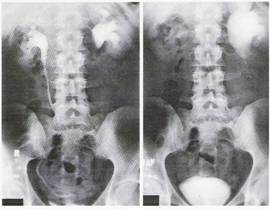

Fig. 2 - Urografie intravenoasa. Observam medie dilatatie pielocaliceala stānga, fara continut īn ureterul stāng. La 15 minute dupa administrarea Furosemidului, sistemul pielocaliceal stāng se largeste, iar cel drept a drenat.